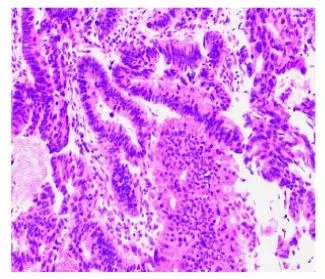

术后病理:1)乙状结肠中分化腺癌,溃疡浸润型,大小7×7×1.5cm,癌组织浸润至浆膜外,浆膜面大量浓痂覆盖,神经累犯(-),腺管累犯(-);2)手术上下切缘(-); 3)区域淋巴结转移情况:肠系膜根部淋巴结(0/8)、肠系膜淋巴结(0/15)(图4)。

图4 病理结果